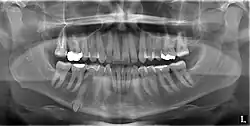

Classifications enable the oral surgeon to determine the difficulty in removal of the impacted tooth. [9] The primary factor determining the difficulty is accessibility, which is determined by adjacent teeth or other structures that impair access or delivery pathway. The majority of classification schemes are based on analysis on a radiograph. The most frequently considered factors are discussed below.

Angulation of tooth

Most commonly used classification system with respect to treatment planning. Depending on the angulation the tooth might be classified as:

This type of classification is based on the amount of impacted tooth that is covered with the mandibular ramus. It is known as the Pell and Gregory classification, classes 1, 2, and 3.[10]

Relationship of tooth to occlusal plane

The depth of the impacted tooth in relation to the adjacent second molar serves as the foundation for this type of classification. This was also given by Pell and Gregory and is known as the Pell and Gregory A, B, and C classification. Relationship to the occlusal plane A-C classes